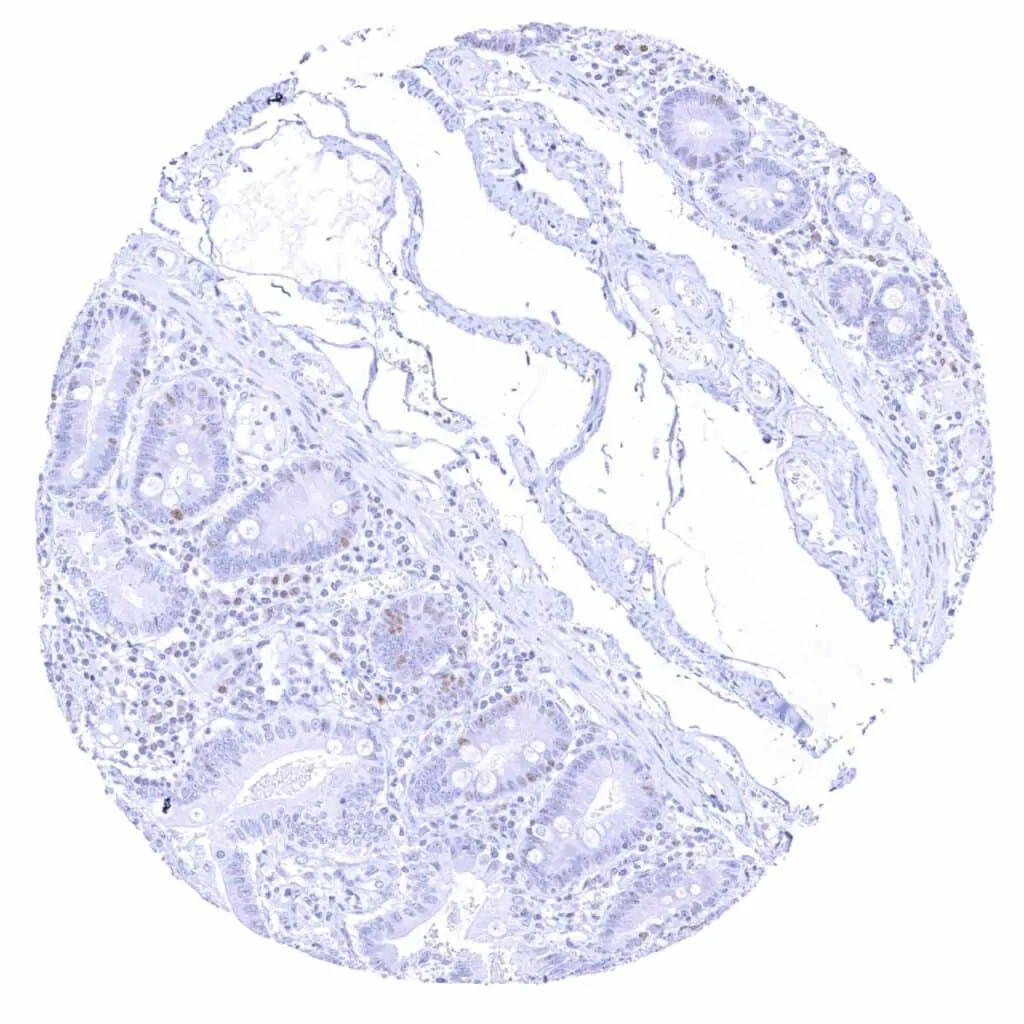

Appendix, mucosa – Weak to moderate Cyclin E1 staining of a subset of crypt cells